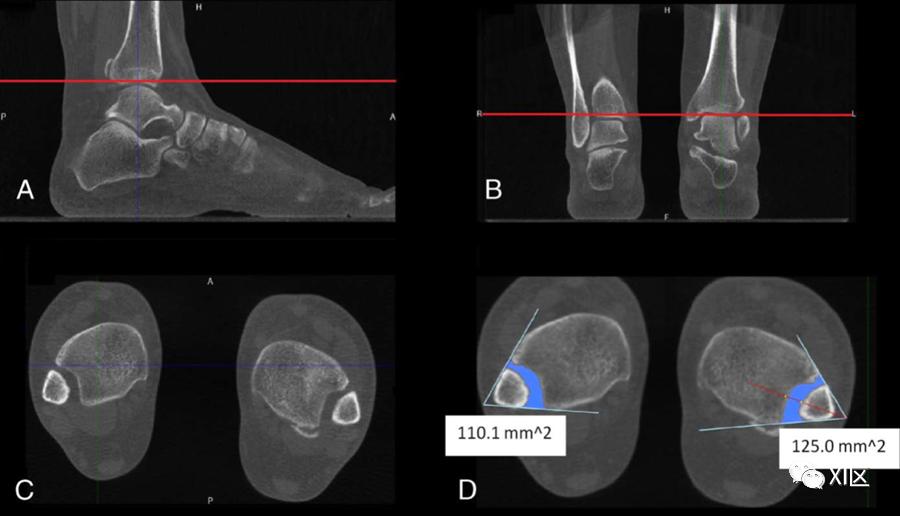

准确及时地诊断联合韧带损伤对于预防慢性踝关节不稳定和预防继发性骨关节炎至关重要。常规CT检查分析了非WB条件下的远端胫腓关节。如前所述,WB-CBCT有助于补充非WB检查的诊断产量;然而,前者的重要性尚待阐明。对于无症状的未受伤踝关节,已经表明,除了内侧间隙外,WB检查似乎在联合测量方面没有明显差异。相反,在临床怀疑有联合韧带损伤的既往踝关节损伤患者中,非WB和WB检查的平均胫腓后距离、间隔和角度测量值存在差异,观察者之间的可靠性接近完美水平。与胫骨平台附近不同水平的对侧未受伤踝关节相比,单侧联合不稳定患者的受伤踝关节显示3D容积WB-CBCT测量值增加;健康对照组中没有这种差异(图3)。

图3:一名40岁患者的WB-CBCT表现为左踝关节疼痛和肿胀。病史显示,两次受伤相隔8年,均接受保守治疗。体检显示中性愈合和足部对齐,但可能会引发一些临床操作。冠状(A)和矢状(B)视图用于确定胫骨平台上方的横向成像平面(红线)。C和D,创建2条相交线,即内侧腓骨皮质和外侧胫骨皮质切迹,有助于确定所选平面上的联合区。WB检查中,左侧联合面积为125 mm2,而对侧面积为110.1 mm2。三维WB-CBCT有效地表征了成年后天扁平足畸形患者的外翻-后足排列(图4)。从平面放射线照相术中采用了用于后足对齐的各种放射测量,并在3D WB-/非WB CBCT图像中进行了验证。这些测量值,包括放射学测量的后足对准角和跟腱/跟骨结节角,与临床测量的后脚对准角的平均值有显著差异。后者低估了外翻对齐的放射学评估10到15度,这表明使用CBCT而不是物理测量的准确性更高。还注意到成人后天扁平足畸形的WB和非WB检查之间的测量差异,其中最可靠的包括内侧楔形至地板距离、冠状前足弓角、矢状长方体至地板距离和矢状舟骨至地板距离(图5)。此外,WB射线照片和WB-CBCT之间的测量结果(如内侧楔形到地板的距离、舟骨到地板的间距、矢状距骨旁第一跖骨角和内侧楔形到第一跖骨的角度)明显不同。